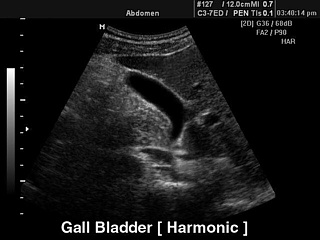

УЗИ желчного пузыря.

Tissue Harmonic Imaging (2-я гармоника).

Tissue Harmonic Imaging (THI™, тканевая или 2-я гармоника) - технология выделения гармонической составляющей колебаний внутренних органов, вызванных прохождением сквозь тело базового ультразвукового импульса. Полезным считается сигнал, полученный при вычитании базовой составляющей из отраженного сигнала. Применение 2-й гармоники целесообразно при ультразвуковом сканировании сквозь ткани интенсивно поглощающие 1-ю (базовую) гармонику. Данная технология предполагает использование широкополосных датчиков и приемного тракта повышенной чувствительности. Улучшается качество изображения, линейное и контрастное разрешение у пациентов с повышенным весом.